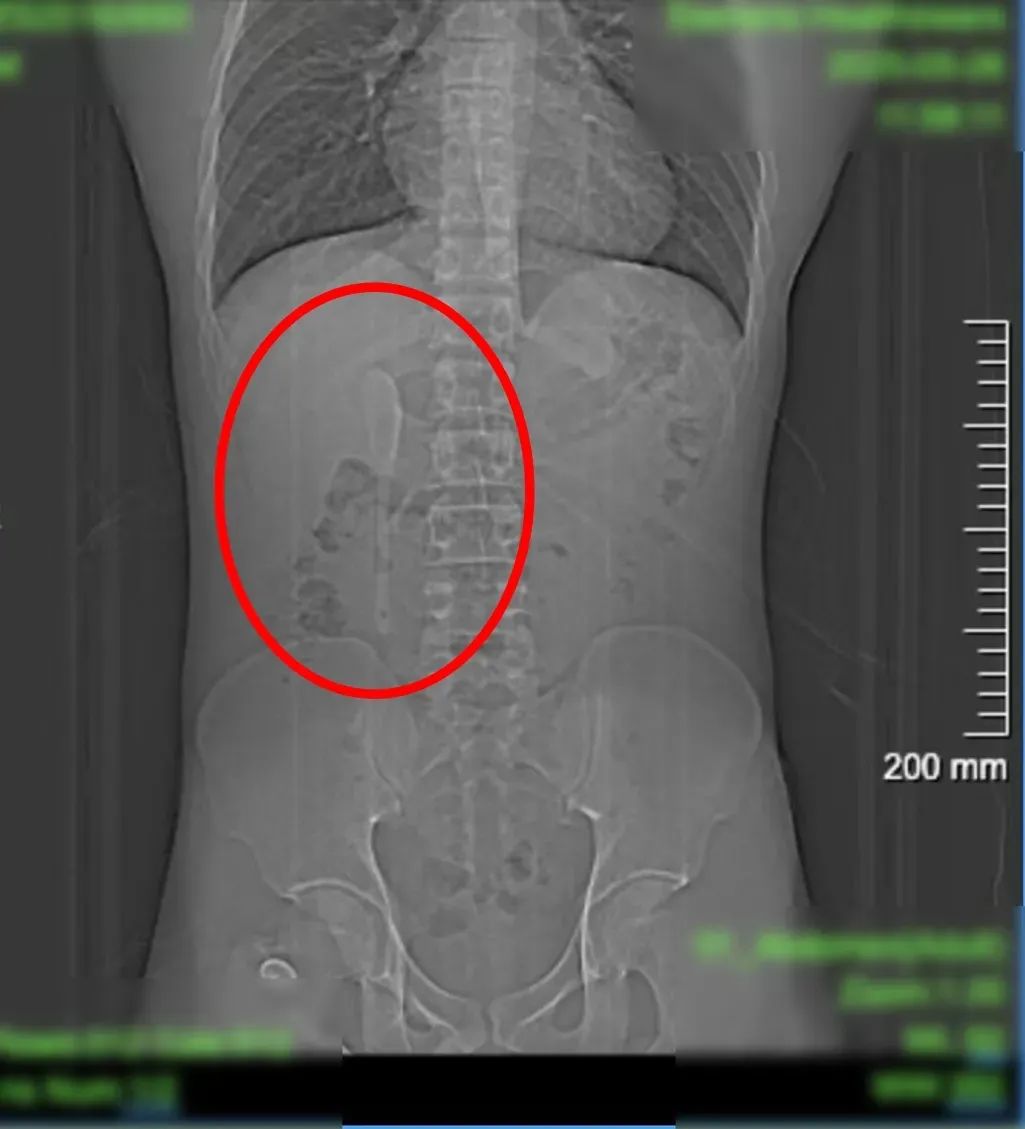

CT显示这个近15厘米长勺状物体

严丝合缝地横亘于

十二指肠球部与降部交界的生理狭窄处

稍有不慎即可能刺穿肠壁

引发腹膜炎或大出血